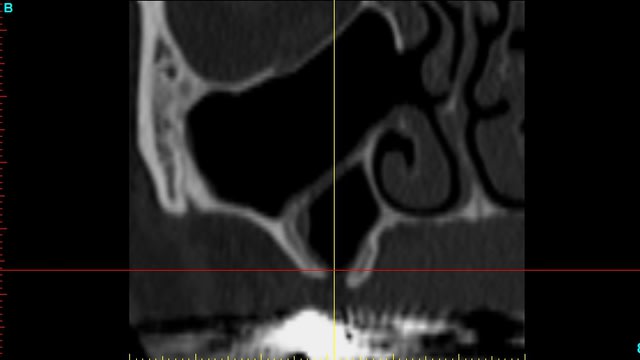

je dois pratiquer un rehaussement de plancher sinusien par volet latéral et je ne sais comment gérer le décollement de la membrane de Schneider au niveau de la communication bucco sinusale

je joins quelques captures pour vous faire une idée

Gérer un décollement avec une CBS c'est déjà assez compliqué mais tu as le septum en plus.

je ne vois pas de septum dans la zone de comblement

pourrais-tu préciser?